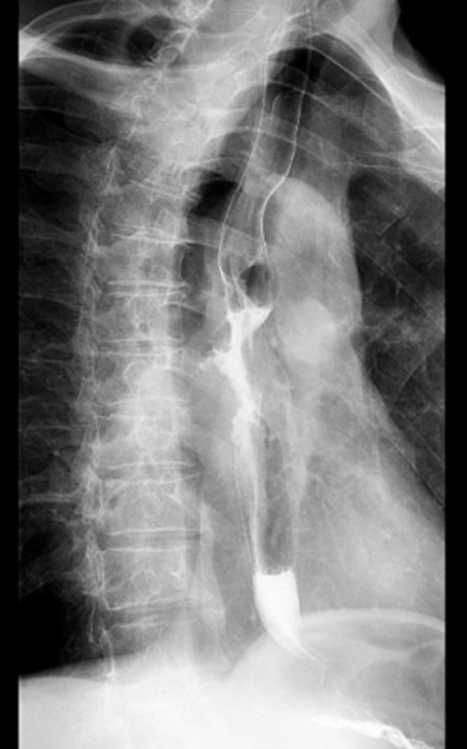

72岁的陈先生(化名),2024年8月开始出现进食梗阻及呛咳,我院增强CT显示是局部中晚期胸中段食管癌,怀疑食管瘘形成。消化道造影证实了这一猜想。胃镜发现胸中段食管鳞癌伴有管腔狭窄。经我院食管癌多学科专家会诊,建议留置营养管,一般情况改善后先行全身治疗,适时局部治疗。患者入院后行内镜下胃管置入术,抗感染治疗后给予全身治疗,经治疗后,患者病情得到持续好转,生存时间已超过16个月,且食管瘘愈合,拔除营养管后,患者实现了经口进食,生活质量显著提升。

治疗前食管癌性狭窄与造影剂经瘘口外漏